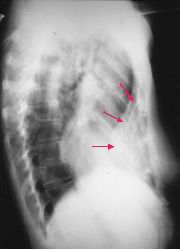

>50%